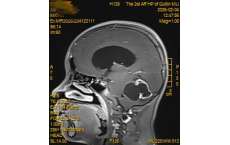

七旬高危患者命悬一线!二附院救治脑动脉瘤破裂合并重症心衰老人

72岁黄奶奶因右侧大脑前动脉瘤破裂致蛛网膜下腔出血,合并左侧硬膜下血肿及严重心脏瓣膜病、慢性心力衰竭,病情极危重。桂林医科大学第二附属医院神经外科联合心血管内科、麻醉科开展多学科协作,成功实施一次性开颅动脉瘤夹闭+血肿清除术,并通过24小时精细化神经重症监护,有效维护心功能、防控并发症,最终实现意识恢复、功能改善并顺利出院,彰显高危合并症下急危神经重症的综合救治能力。